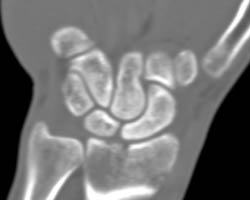

Scaphoid Fracture